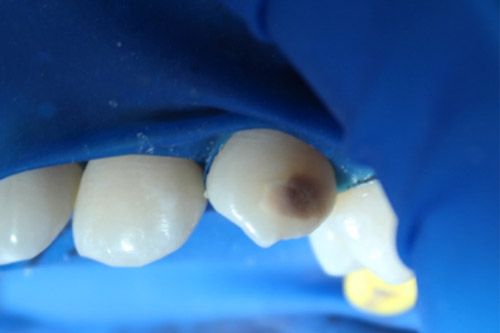

Se utilizó una lámpara para transiluminación Radii plus de SDI, la cual cuenta con una punta de diagnóstico con un led blanco que da dos intensidades, se observa que la luz no atraviesa la zona afectada, (esto quiere decir que la lesión es muy profunda y no podrá ser infiltrada con icon, por lo que se decide arenar o utilizar microabrasión).

Se realizó aislamiento absoluto.

Se decidió utilizar un aeropulidor con bicarbonato Detarfar de Eufar por 1 minuto, con la finalidad de remover el tejido afectado.

Se observó que una cavidad se había formado, los bordes de esta se grabaron con Icon etch por 2 minutos.